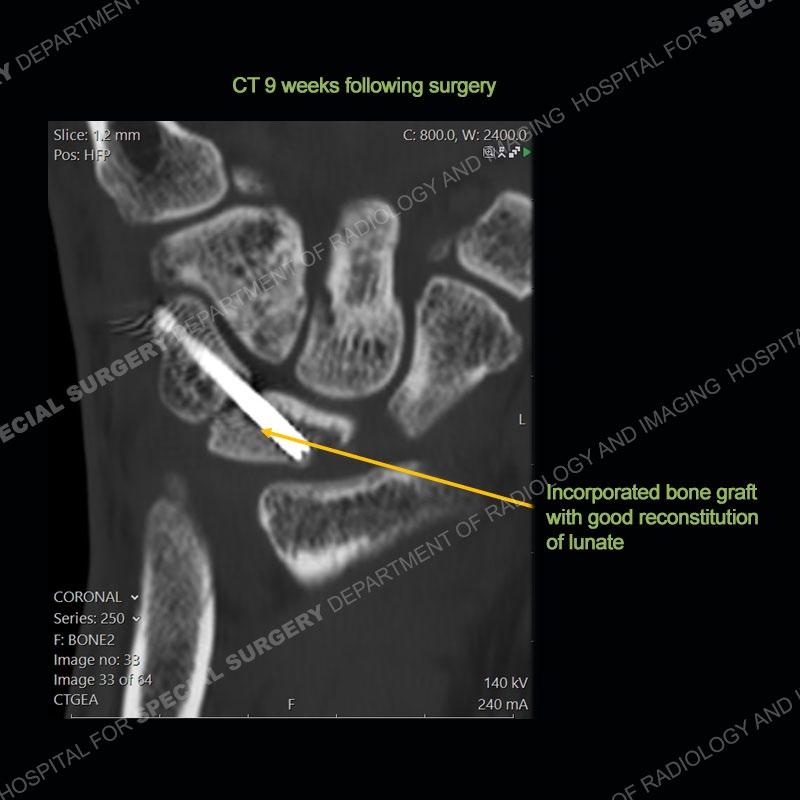

The treatment as the underlying cause of Kienbock’s remains somewhat elusive. Prior to collapse, osteotomies to decrease load or shearing forces to the lunate may be helpful. Once collapse and arthritis have been engendered, fusion and carpectomy have been performed. Now, the role for vascularized bone grafting is being investigated with long term results still being somewhat lacking. Given the young age of the second patient and lack of adjacent, advanced cartilage wear, a vascularized bone graft was performed. The area of necrotic bone was excised, a vascularized bone graft from the distal femur was harvested, and then using microsurgical technique it was grafted to the lunate. A temporary fixation was performed and once the graft was incorporated, the fixation hardware was removed. Although still early in the postoperative period, the patient is doing well.